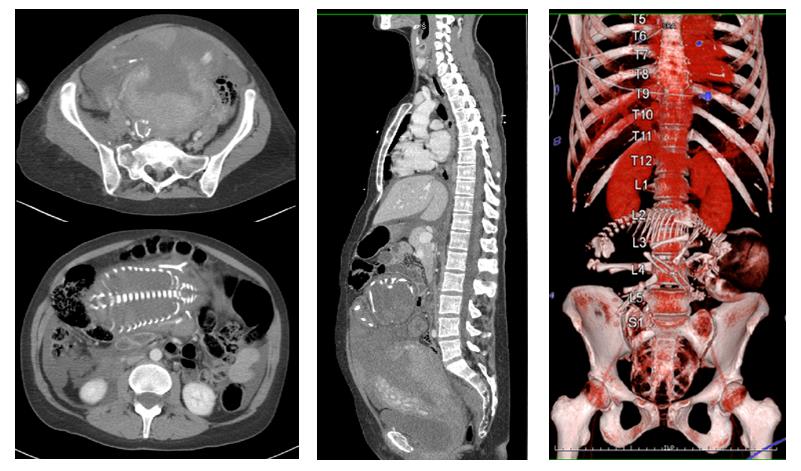

- Accidentes automovilísticos: se trata de la principal causa de politraumatismos en este grupo de pacientes. Los cambios fisiológicos que ocurren durante el embarazo, como el aumento del tamaño del abdomen y la alteración del centro de gravedad, aumentan el riesgo de lesiones en caso de accidente. Además, muchas mujeres no utilizan cinturones de seguridad de manera adecuada, lo que incrementa la gravedad de las lesiones (3) (Fig. 1).

Fig. 1.